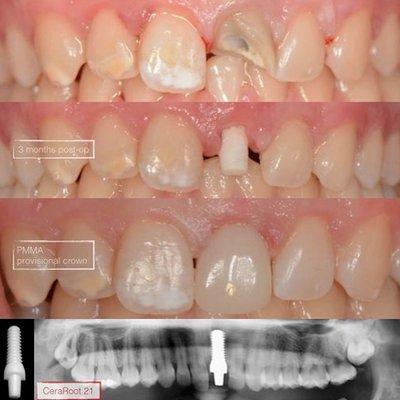

CeraRoot Zirconia Implants - Holistic Dentistry

“I met Dr. Xavi Oliva, CEO of the company, when I was doing a research on dental implants. After talking to numerous dentists and cross-referencing the info on various websites I came to conclusion...

About|Ceraroot Zirconia Implants is a leading provider of holistic dentistry solutions in Santa Monica, CA. With over 15 years of clinical study, their ceramic implants are highly functional and easy to use, offering a natural and aesthetic solution that avoids the displeasing appearance of metal titanium implants. Approved by FDA, Health Canada, Europe Community, and Australia's TGA, Ceraroot implants are made of high-strength ceramic, designed to achieve the highest functional and esthetic demands. Their commitment to quality and innovation has made them a trusted choice for patients and professionals seeking long-lasting satisfaction and optimal implant placement. Generated from the website